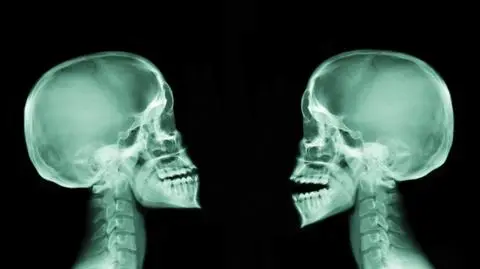

Grafikę, która miała pokazać różnice w budowie czaszki kobiety i mężczyzny opublikował jeden z popularyzatorów nauki. Zamieszczona w mediach społecznościowych ilustracja wzbudziła sporo kontrowersji i wywołała wiele dyskusji. Dlaczego jest pozbawiona rzetelności? Poznaj wyjaśnienia ekspertki.

Różnice w czaszkach kobiety i mężczyzny

W mediach społecznościowych regularnie pojawia się wiele kontrowersji. Ostatnio wywołała je rycina, którą podzielił się na portalu X popularyzator nauki. Ilustracja ma przedstawiać różnice w kształcie, strukturze i budowie czaszki między kobietami i mężczyznami. Z grafiki wyniki, że czaszka męska ma mieć "wyraźne łuki brwiowe" i "większe wyrostki sutkowate kości skroniowej", a kobieca ma się charakteryzować "gładką, bardziej pionową kością czołową" i "małymi wyrostkami sutkowatymi kości skroniowej". Dodatkowo czaszka męska jest na ilustracji wyraźnie większa niż kobieca.

Rycina dwóch czasek zwróconych przodem przypisywana jest radzieckiemu paleontologowi i krąży przede wszystkim w rosyjskim Internecie. Nie udało się ustalić natomiast, skąd pochodzi druga ilustracja, w której czaszki zwrócone są bokiem. Grafika ta wywołała ogromne oburzenie internautów.

- Z pewnością nie są to materiały przygotowane w sposób profesjonalny i rzetelny, nie są też wystarczająco szczegółowe - oceniła specjalistka. Dodała, że aktualnie jest bardzo wiele czaszek, które nie mają cech wyrażonych skrajnie w kierunku męskim lub żeńskim.

- Przesłana grafika w żadnym stopniu nie prezentuje sytuacji uśrednionej - przeciwnie, zobrazowane są na niej skrajności w budowie morfologicznej czaszki męskiej i żeńskiej - podsumowała antropolożka.